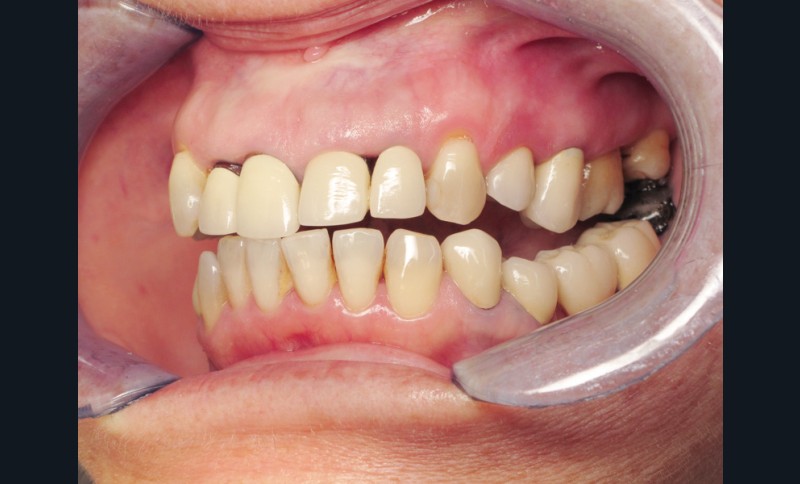

Madame J., âgée de 63 ans, consulte pour des douleurs chroniques localisées au niveau de 14 et de 21. L’examen endobuccal révèle la présence de prothèses anciennes, de soins conservateurs et d’un implant posé depuis 4 ans. On note une inflammation généralisée du parodonte superficiel avec présence de plaque et de tartre et une mobilité de certaines dents dont les incisives maxillaires droites. Dès ce stade, le surguidage antérieur du couple 11/12, reconstitué par des couronnes solidarisées, est à mettre en relation avec la souffrance parodontale observée (fig. 1).

Une inflammation de la zone péri-implantaire (24), en relation avec le motif de la consultation est également visible dès ce premier examen.